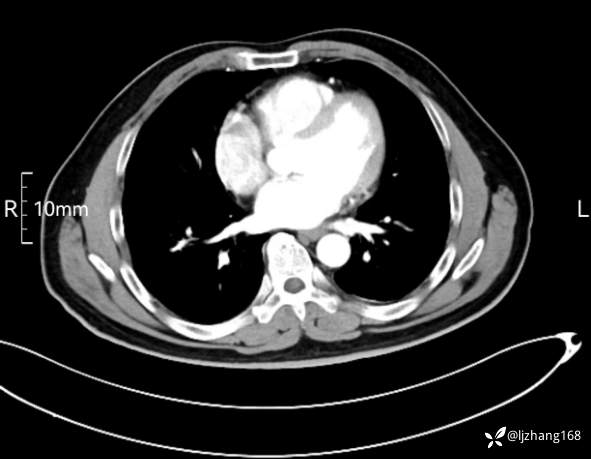

中年男患,右肺团片影,炎症0R肿瘤?

辅助检查:糖化血红蛋白12.3%。肺炎支原体IgG、IgM、呼吸道合胞病毒均未见明显异常。胸部CT:右肺上叶阻塞性肺炎。